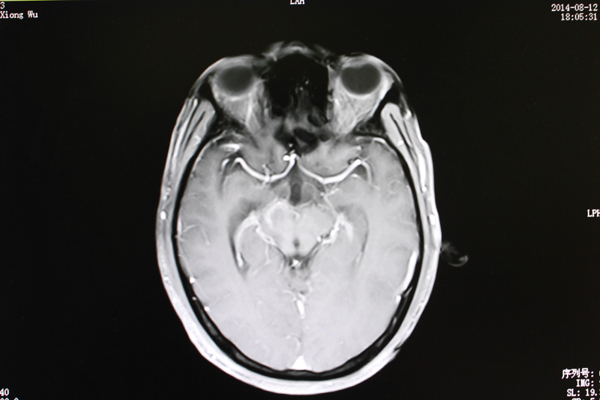

脑干长肿瘤不能开刀?射波刀一解难题

41岁的黄先生在平南县从事农贸生意,家中儿女双全,本过着幸福的生活。然而两个月前黄先生莫名出现头晕,左耳耳鸣的情形,以为是小毛病就不太...